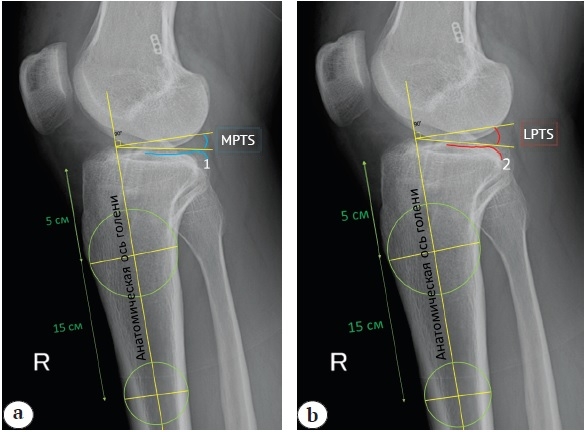

Technique for measuring MPTS and LPTS on X-rays

Measurements were conducted using the Radiant DICOM Viewer, v. 2021.2 (Medixant, Poland). To minimize measurement errors, two senior physicians from the department independently performed measurements, and the average value of all measurements was determined.

The posterior tibial slope was determined on lateral-view knee radiographs relative to the anatomical axis of the tibia. This was determined by inscribing two circles on the proximal part of the shin, 5 and 15 cm distal to the joint surface, and drawing a line connecting their centers. The surface of the medial (blue line) and lateral (red line) tibial plateaus was determined (Fig. 1). The angle between the tangent and the central axis of the tibia was measured. MPTS and LPTS were determined using the formula:

MPTS and LPTS = 90° - the angle between the anatomical axis of the tibia and the tangent drawn along each plateau.